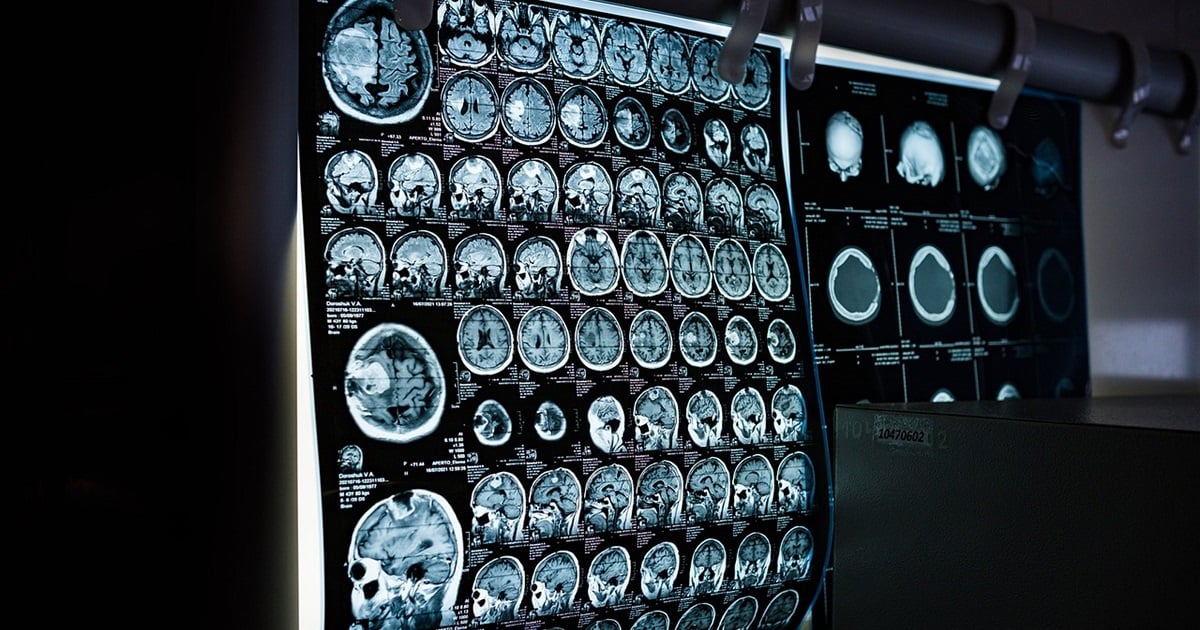

Magnetic resonance imaging (MRI) is an established imaging modality for the multiparametric evaluation of tissues in many pathologies, ranging from degenerative and inflammatory illnesses to malignancy. Traditionally, MRI utilizes strong magnetic fields and radio waves to generate intricate images of the interior of bodily structures. Nonetheless, the analysis of these scans can be laborious and necessitates a considerable degree of knowledge. In recent years, the ongoing technical advancement of equipment has resulted in the creation of sequences that deliver both anatomical and functional metabolic information.

The manual interpretation and processing of medical images is difficult and susceptible to errors, leading to the oversight of minor lesions that can occasionally result in misdiagnosis. Developing advanced signal processing techniques for various low-level (such as image reconstruction, contrast enhancement, and image segmentation) and high-level applications (including interpretation, classification, and assessment of image findings in diagnoses, as well as the planning, monitoring, and evaluation of treatment) in medical imaging is essential for precise diagnosis and tailored treatment. These applications require innovative, sophisticated methodologies in fields including, but not limited to, computer vision, artificial intelligence, machine learning, pattern recognition, and evolutionary algorithms and optimization. Advancements in artificial intelligence (AI), particularly deep learning (DL), have enhanced the interpretation of magnetic resonance imaging (MRI) data, allowing for AI-assisted medical picture diagnostics and prognoses. Nevertheless, the majority of deep learning models are regarded as "black boxes." There exists a necessity to elucidate deep learning models so that domain experts can have confidence in these high-performance models.

AI can enhance MRI processes by automating multiple phases of the imaging process, including planning, data acquisition, reconstruction, parameter mapping, and segmentation, thus improving total MRI efficiency. Artificial intelligence can surmount difficulties typically faced in MRI, like enhancing patient motion tolerance. It can also improve the quality of MRI scans to more correctly detect disorders and inform subsequent medical interventions.